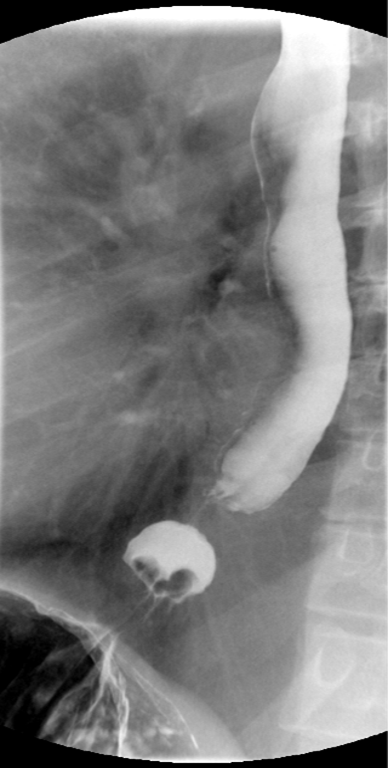

- Method—Cervical:

- Start with the patient in the upright lateral position.

- Ensure the fluoro machine is set to 4 images per second (rapid sequence).

- Explain to the patient that you are going to have them take a "comfortable mouthful" of barium and that they will need to hold it in their mouths until you count to 3.

- Make sure they understand that they are not to swallow until the count of 3.

- Once the patient has taken the "comfortable mouthful" of barium, center the fluoroscope on the cervical esophagus.

- Once the fluoroscope is properly positioned, begin counting. On the count of 2, begin taking rapid sequence images of the contrast material bolus as it moves through the cervical esophagus

(key image 1)

- Take the fluoroscope off rapid sequence.

- With the patient in the lateral position, obtain a spot film of the pharynx and cervical esophagus while they phonate the letter "e"

(key image 2).

- Cervical images are obtained in the lateral and AP projections as the patient swallows thick barium.

- Cervical image are obtained using rapid sequence fluoroscopic spot films at a rate of 4 frames per second.

- To time this appropriately, you will count to 3. You will begin to take images on 2, the patient will swallow on 3.